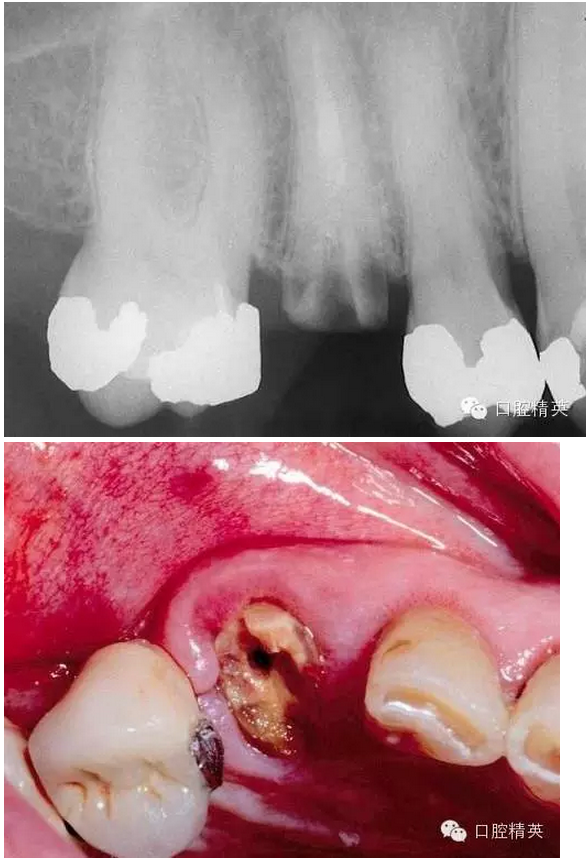

看看一個(gè)雙尖牙根的拔除 ,我常常對(duì)年輕的大夫說,我覺得難拔的不是下頜阻生智齒,而是有雙根的上頜雙尖牙,特別是一些正畸需要拔出的健康牙。

拔除后軟硬組織的創(chuàng)傷都很小。